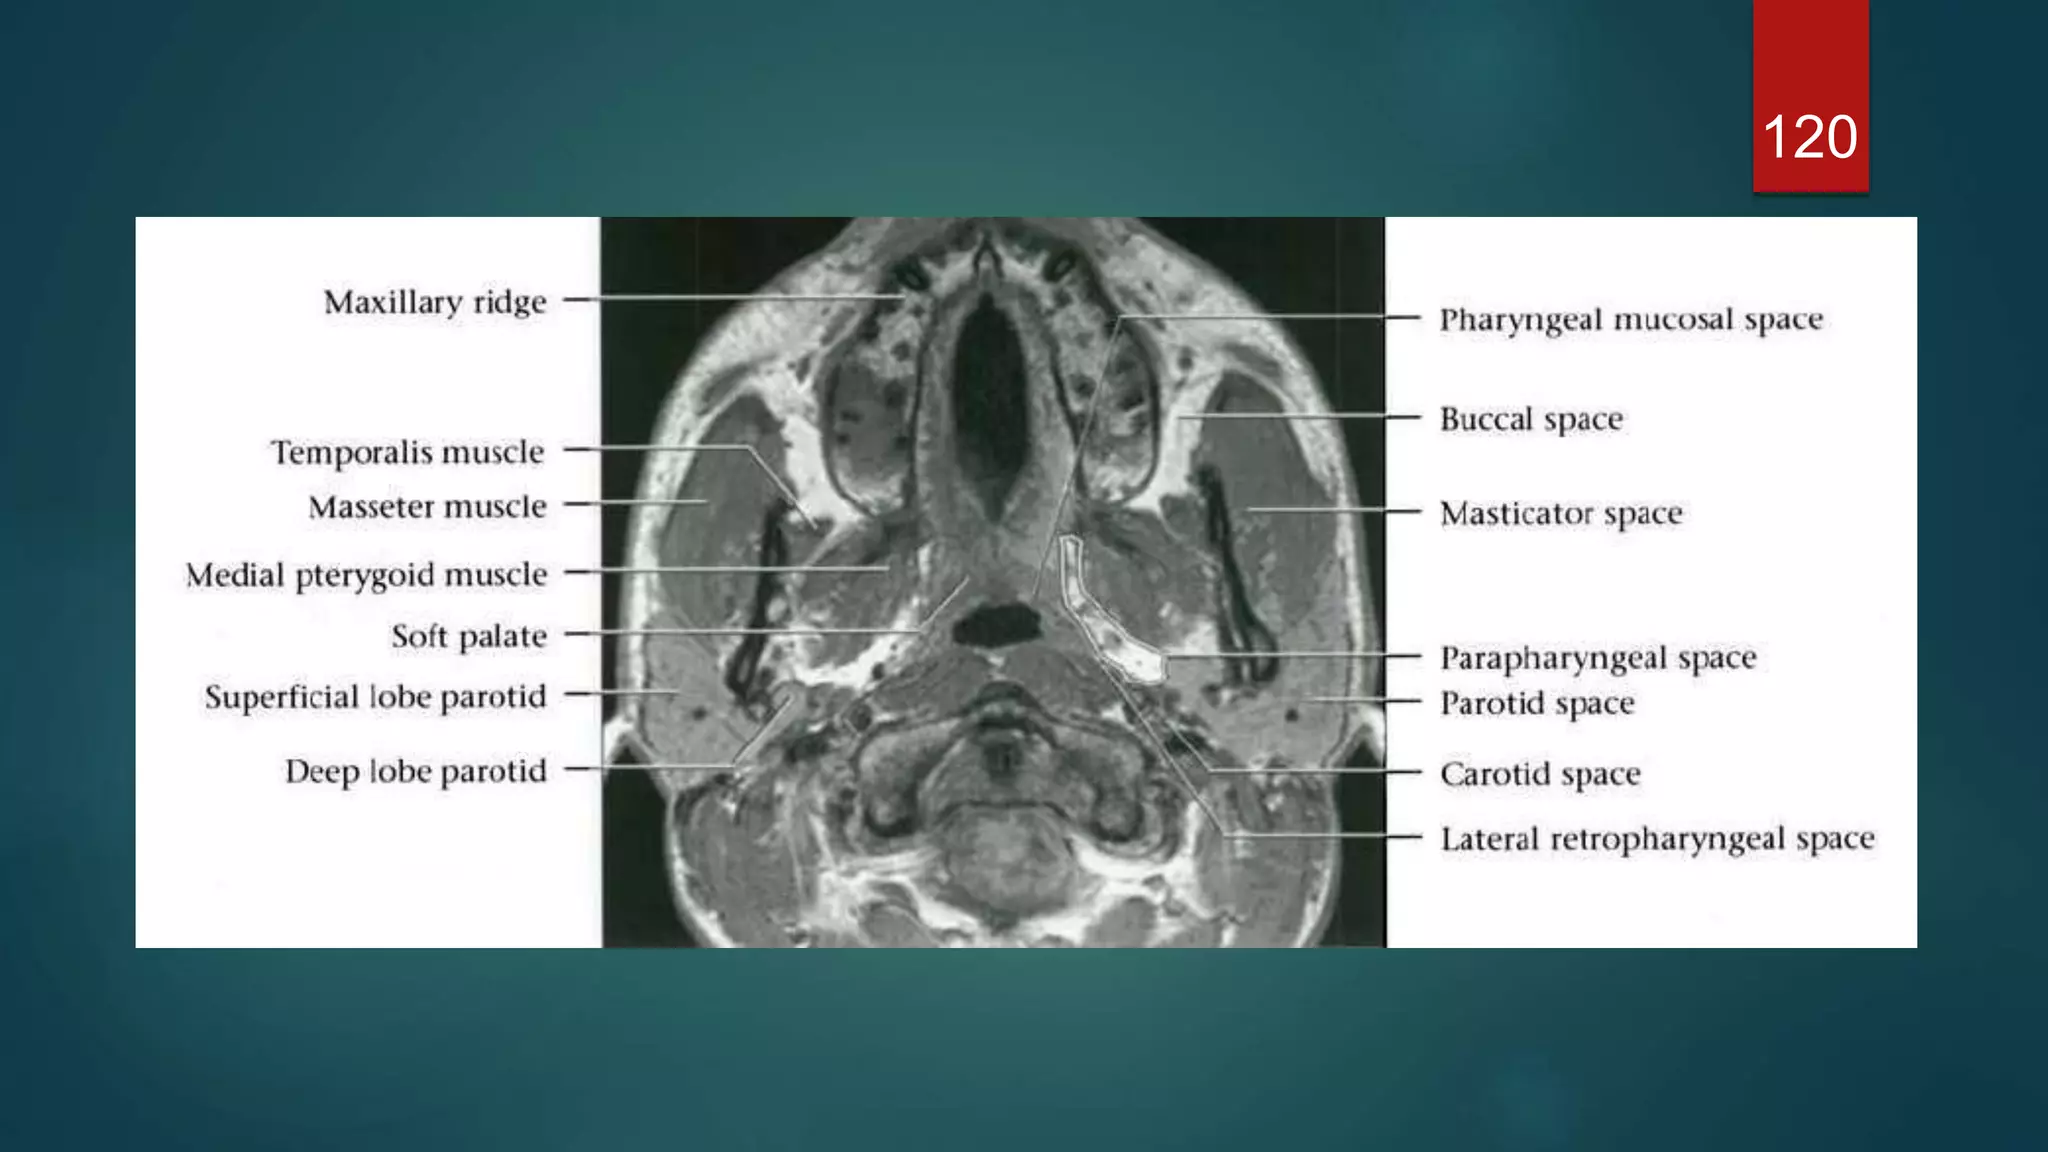

120

MRI